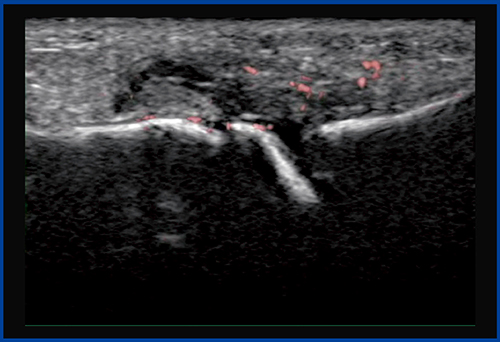

SMIは,微細な血流を観察するために開発された技術だが,注射の状態の観察にも応用できる。

図11は,指屈筋腱の腱鞘炎(ばね指)症例の短軸像で,腱の周囲の腱鞘(黒い部分)が腫れているのがわかる。腱は1本ではなく,深指屈筋腱と浅指屈筋腱が組み合った構造をしている。注射をしながらSMIで観察すると,腱鞘をはじめ,腱と腱の間にも薬液が入る様子が観察できる(図12)。確実な治療効果を得るために,SMIでの観察が有用であると言える。

このようにSMIを活用することで,今後,運動器領域の治療が変わっていくものと考えられる。

図11 指屈筋腱腱鞘炎の短軸像

●浅指屈筋腱

●深指屈筋腱

図12 指屈筋腱腱鞘炎に対する注射中のSMI画像

腱鞘や腱と腱の間に薬液が入る様子が確認できる。